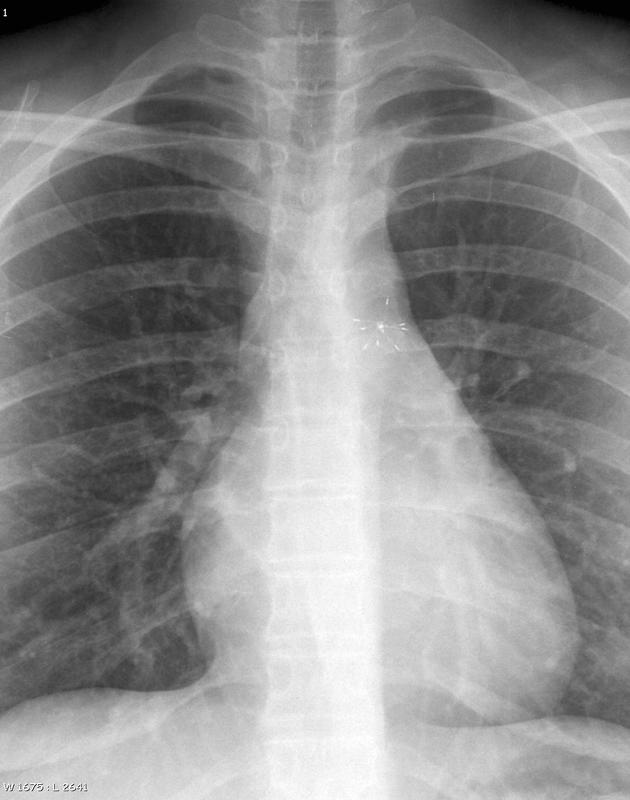

clam shell PDA